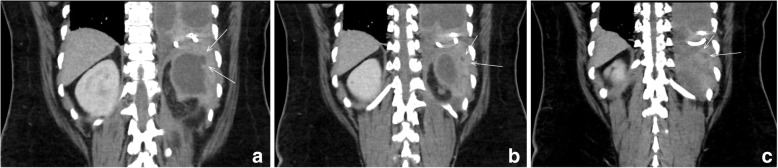

Fig. 3.

Computed Tomography results showing sequential coronal cross sections of the patient’s abdomen extending posteriorly with the white arrows indicating the posteriorly and superiorly extending tract from the renal cyst to the diaphragm. (Anterior to Posterior (Left to Right): a, b, and c)